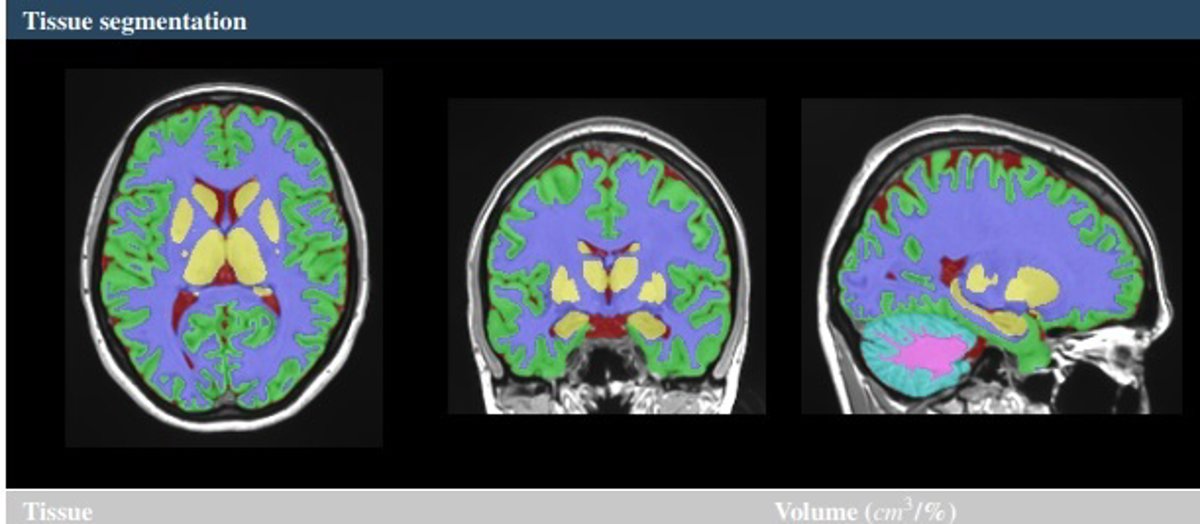

Vol2Brain es capaz de analizar hasta 135 regiones del cerebro, a partir de imágenes de Resonancia Magnética (RM) del cerebro. Ofrece DATOS sobre los volúmenes de los tejidos de la cavidad intracraneal (ICC), así como de algunas áreas macroscópicas como los hemisferios cerebrales, el cerebelo y el tronco cerebral. Además, proporciona también los volúmenes e índices de asimetría de estructuras corticales y subcorticales, de gran importancia en el ámbito neurológico, así como medidas de grosor cortical.